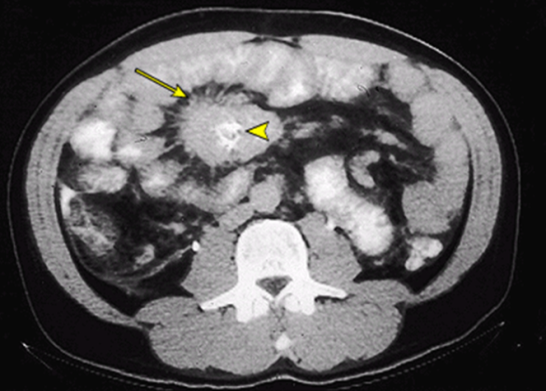

NB-a yad cisimlər qəbul edilmiş qida ilə daxil olurlar. Klinik təcrübədə balıq, quş və qoyun əti sümükləri, onların fraqmentləri kimi yad cisimlər çoxluq təşkil edir. Uşaqlar arasında düymə, qəpik, uşaq oyuncaqlarının kiçik detalları və fraqmentlərinin udulması hadisələrixeyli çox rast gəlir. Qadınlarda iynə, sancaq, düymə udulması və onların MBT-na keçməsi hadisələrinin tezliyi yüksəkdir. Suisid, işgəncələr və fiziki zorakılıqlardan yayınma məqsədi ilə metal əşyalar – çay qaşığı, yemək qaşığı, çəngəl, bıçaq tiyəsi və özü, mıx(lar) və ya mıx topası və b. cisimlərin udulmaqla bağırsağa düşməsi halları çox müşahidə edilir. Bitki mənşəli həzm olunmayan hissələr (bitkilərin gövdələrinin və ya budaqlarının fraqmentləri), qatranşəkilli maddələr həzm yolunun bu və ya digər hissələrində toplanaraq fitobezoarların (şək 6. ), udulmuş tüklər isə trixobezoarların əmələ gəlməsinə səbəb olurlar. Az hallarda öd kisəsi daşlarının fistul vasitəsi ilə bağırsaq mənfəzinə keçməsi və keçməzlik yaratması hadisələrinə rast gəlinir. Səhiyyə praktikasında xüsusilə kənd əhalisi arasında kiçik heyvanların (ilan, qurbağa, həşəratlar) udulması hadisələri də müşahidə edilir.

Şək. 6. Nazik bağırsağın fitobezoarı